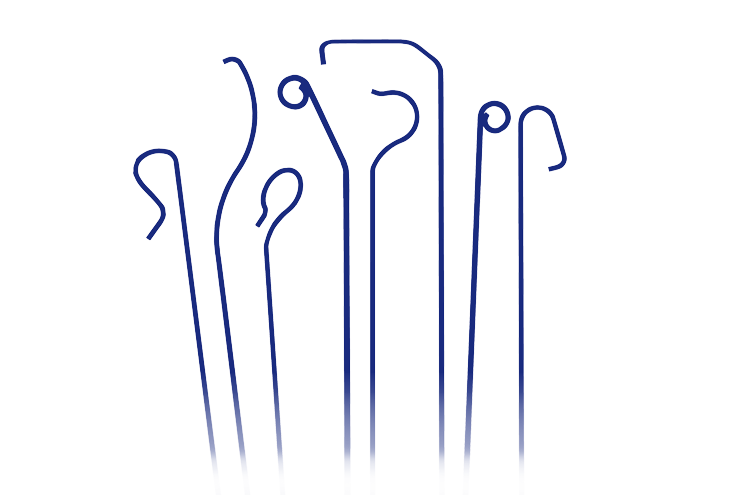

- Mikro katéter

- Vodiaci katéter

- Angiografický katéter